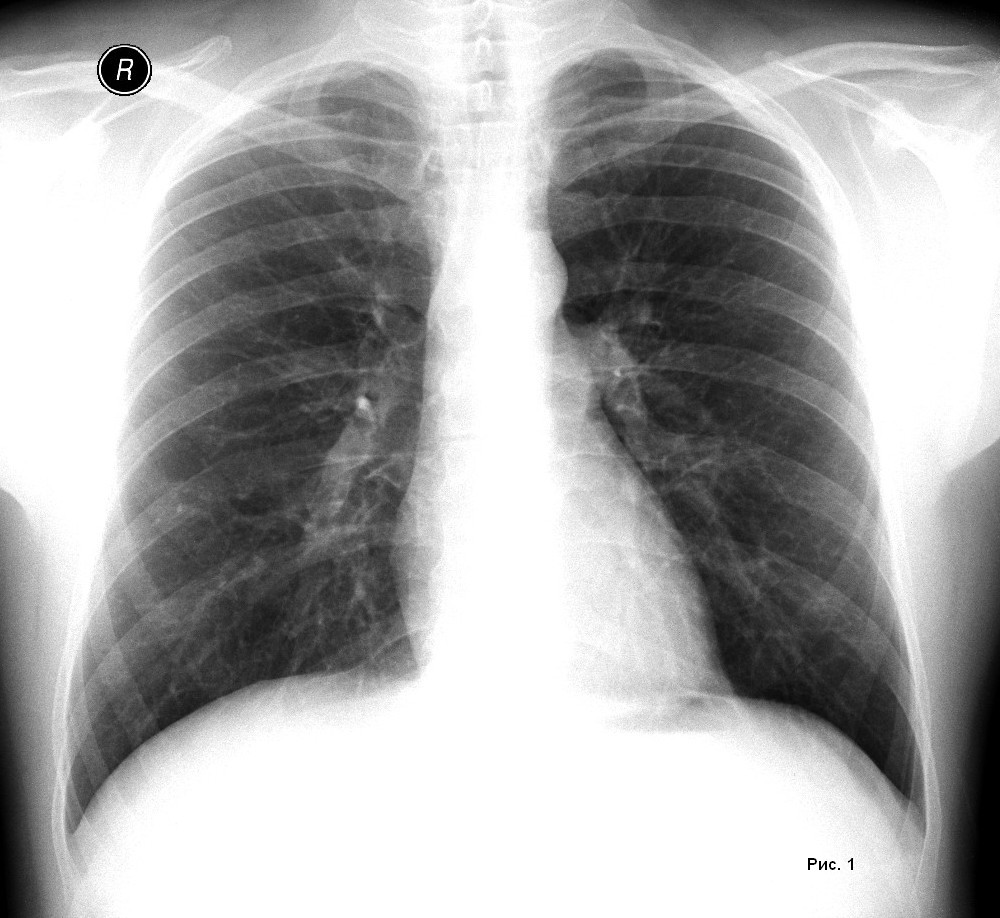

Ключевую роль в этом механизме играет блуждающий нерв – один из главных коммуникационных путей между мозгом и внутренними органами, включая лёгкие. Учёные с помощью генетических методов “выключили” определённые сенсорные нейроны у лабораторных мышей с раком лёгких. Результат оказался неожиданно сильным: рост опухоли снизился более чем на 50%.